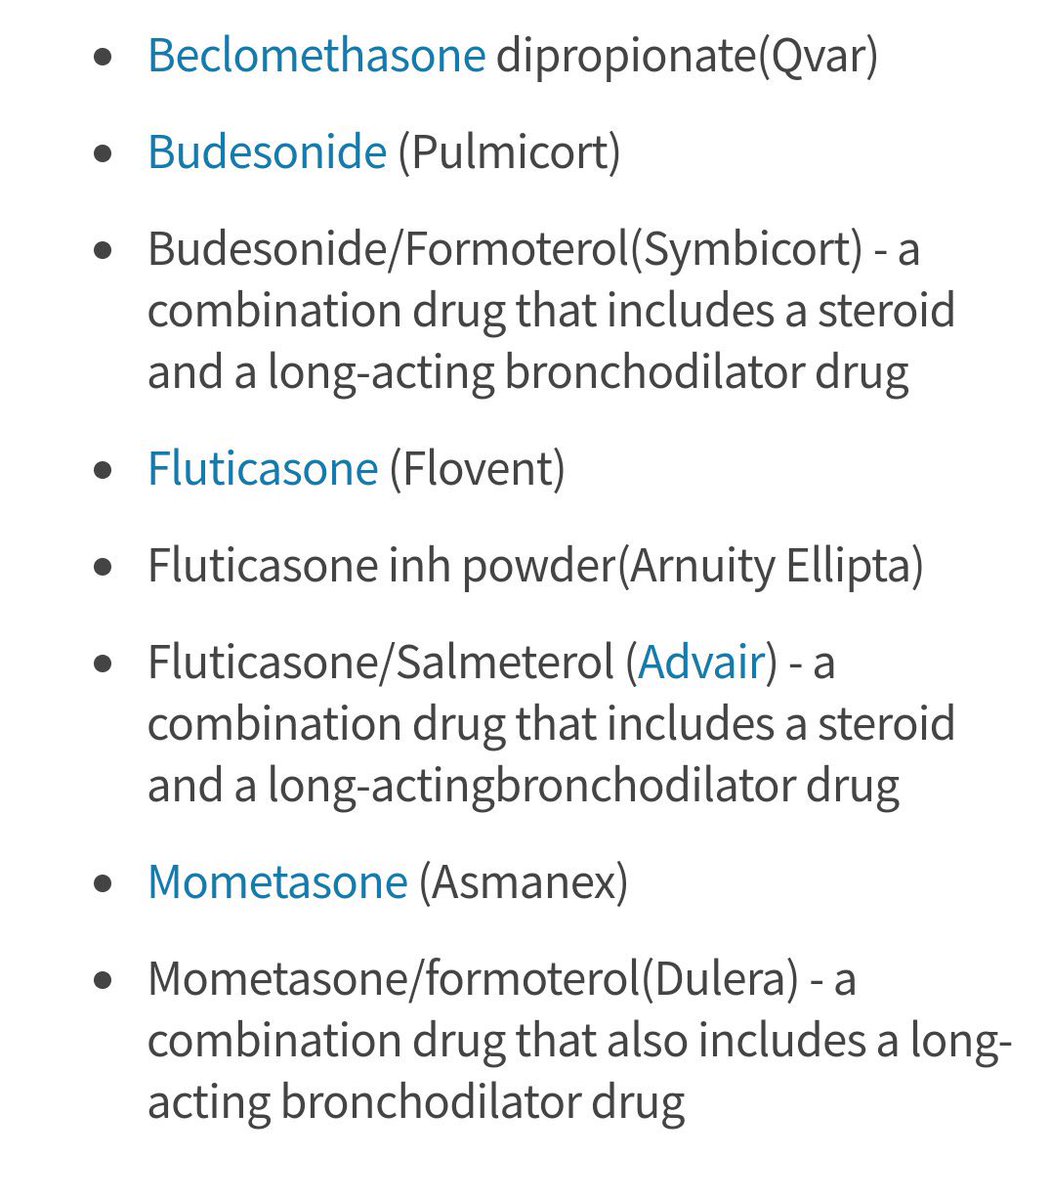

بعد مايرد طبيعي تبدأ الخطه كالتالي

وهنا دايما خطة الchronic تبدأ

يلا نبدأ خطة المزمن #chronic /

if symptom less than 2 days per week Will be #intermittent(before mild) & Give him: #step 1

#Step 1: SABA (short acting beta agonist )PRN

يعني احد ادوية SABA يعني عند اللزوم

👇🏻

وهنا دايما خطة الchronic تبدأ

يلا نبدأ خطة المزمن #chronic /

if symptom less than 2 days per week Will be #intermittent(before mild) & Give him: #step 1

#Step 1: SABA (short acting beta agonist )PRN

يعني احد ادوية SABA يعني عند اللزوم

👇🏻